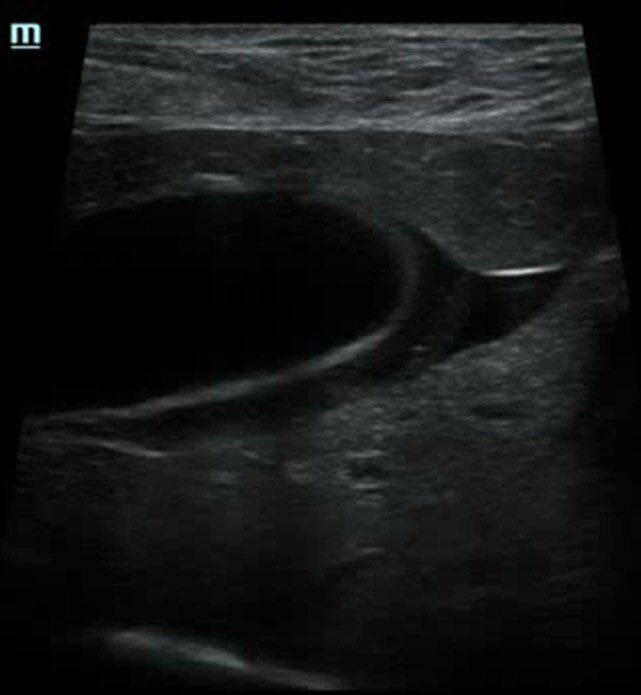

Собака Булка поступила на прием терапевта с жалобами на дрожь и болевой синдром, а также рвоту, диарею и одышку. При сборе анамнеза выяснилось, что вчера помимо обычной порции корма Булка получила пельмень со сметаной. Врач отправил собаку на УЗИ, где были обнаружены признаки острого холецистита - выраженное утолщение стенки желчного пузыря и следы свободной жидкости в брюшной полости.

По анализам крови также отмечались выраженная билирубинемия, повышение трансаминаз и умеренный лейкоцитоз. После курса терапии Булка чувствовала себя отлично, а на контрольном УЗИ стенка желчного пузыря выглядела абсолютно нормальной.